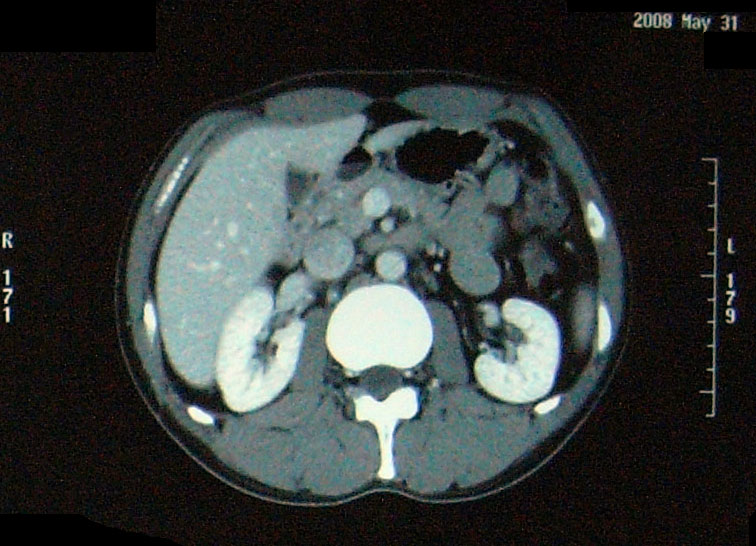

【単純CT】

問題なし! 【腫瘍マーカー】 HCGβ:<0.1 問題なし! 次は9月!

問題なし! 【腫瘍マーカー】 HCGβ:<0.1 問題なし! 先週検査でした。 今日はその結果。 今日は珍しく先生が寝ぼけていました(笑)。 次回のレントゲン検査の受付票を何回も出し間違えた。 1回目:診察後清算も済み帰ろうとした所で俺が気がついた。「これ、画像データCDR作成申込書じゃん・・・」 2回目:受付で上記を伝え、看護婦さん:「すいませ~ん!これで大丈夫ですか?」 確認すると今度はXP検査受付票なので「OKです!ありがとうござ・・・ん?!?これ検査日が今日です・・・・」 看護婦さんダッシュで戻っていきました。 3回目:看護婦さん:「今度は~~」 俺:「間違いないです!」 看護婦さん:「先生寝ぼけてるんですよぉ~」 次は3月!

問題なし 【腫瘍マーカー】 HCGβ:<0.1 問題なし 【中性脂肪】 219→137 基準内(38-193)に入った 今回、検査画像をデータでもらってきた。 後腹膜の転移した箇所の前後4枚を2003年から2010年まで並べてみた。 http://gomatsushita.gozaru.jp/ct/album/index.html 2006/7/18の画像を見ると腫瘍がハッキリ見える。 BEP2クール後の9/27の画像では明らかに縮小もしくは消滅。

【CT画像】

単純CT:特に変化を認めず。 【腫瘍マーカー】 HCGβ:<0.1 問題なしでした! 今日は画像はありません。 理由は、病院側でデジタル化が進んでいて、PCモニターでの画像確認となったからです。 今日はフィルムも用意されませんでした・・・・。 先生曰く、そのうちフィルムもなくなるだろうと。 そのときにはCD-R等に焼く対応もするようになっているはずだと。 早くデータで画像がほしい。その時はたくさんアップしますw。 次回は2月です。

今回からCTの造影剤はありませんでした。

勘違いしてた・・・ なので単純CT。 横になって撮るだけなので非常に楽ですね。その分撮影される画像も解像度が低くなりますが・・・ しかし、思えば2005年末頃の単純CTからリンパ転移が疑われ始め、その次からはずっと造影剤を使用したCTだったわけだ。 2008年末の今、やっとそこへ戻ってきたという感じがした。 検査後の帰り、病院の最寄り駅のパン屋で朝食。 改札横に店があるのでガラス越しに行き交う多くの人を眺めながら思う。 2006年の入院中、ヨメも色々思いながらここを通ったんだろう、と。 何ヶ月も。 暑い日も雨の日も。 ただただ「感謝」あるのみです。 本日の検査結果は12/8。